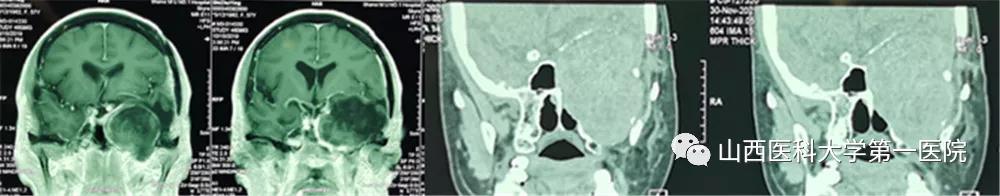

患者是一名老年女性,早在7年前诊断为颅底“胆脂瘤”,7年来已经接受了三次开颅手术治疗,近期出现的头痛、视力减退、面部麻木等症状预示着肿瘤可能再次复发。经MRI和CT检查后发现其肿瘤不仅复发,而且较以往体积明显增大,最大直径达8.5cm,最麻烦的是肿瘤所处的位置非常“尴尬”,像一颗“*弹炸**”深深地卡在了中颅底,约1/4部分瘤体位于颅腔,其余3/4凸向翼腭窝、颞下窝。“巨大的肿瘤体积、复杂的解剖位置、既往多次手术史”等不利因素,为本次手术治疗带来了巨大挑战。术前由医务处牵头组织由口腔颌面外科、神经外科、麻醉科、手术室等组成的多学科团队对手术方案进行了周密部署,对术中风险进行了充分评估并制定了应急预案。

经过对“手术入路、硬脑膜修补、颅底缺损重建、颈内动脉和海绵窦等毗邻结构保护”等系列高风险环节的反复研究,最终定为由口腔颌面外科先行颈-颌入路、上颌骨、颧骨部分切除,充分显露后先切除颅外3/4部分瘤体,再通过颅底骨缺损“窗口”由神经外科完成颅内部分瘤体的切除与硬脑膜的修补,最后采用股前外侧肌皮瓣游离移植修复颅底、翼腭窝、颞下窝巨大无效腔。为了使手术方案进一步可靠,口腔颌面外科团队术前采用数字化技术对手术入路进行了虚拟验证,并从三维立体方向对肿瘤周围的重要结构进行全方位掌握。